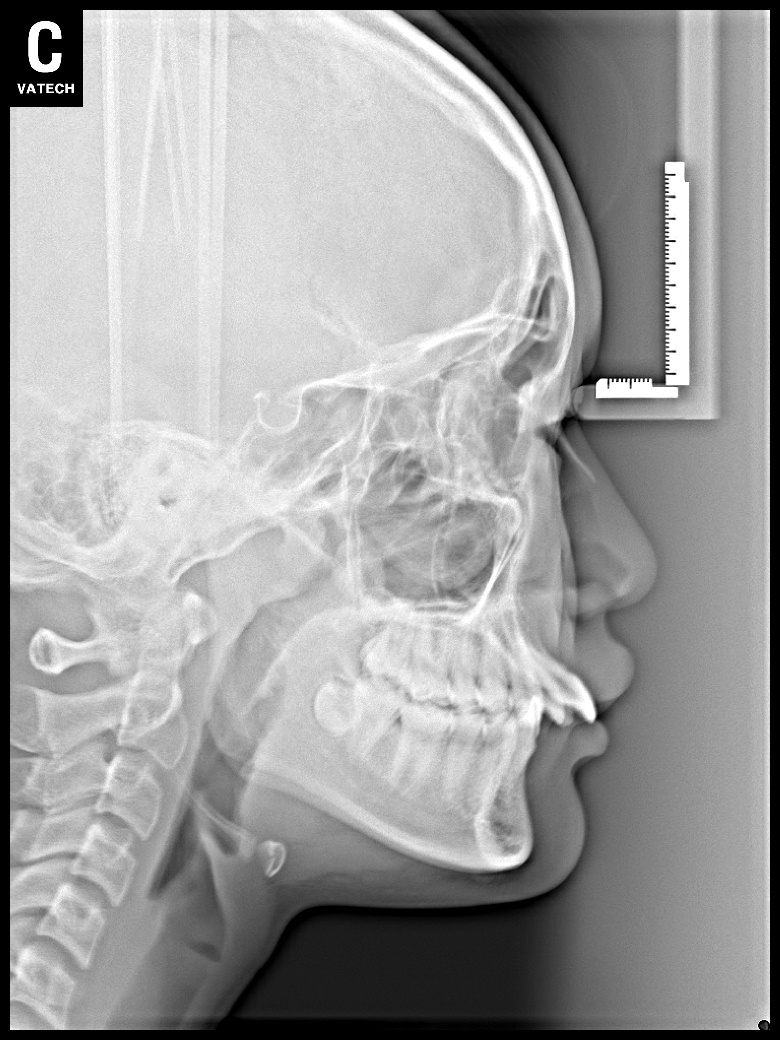

치료 후 사진입니다.